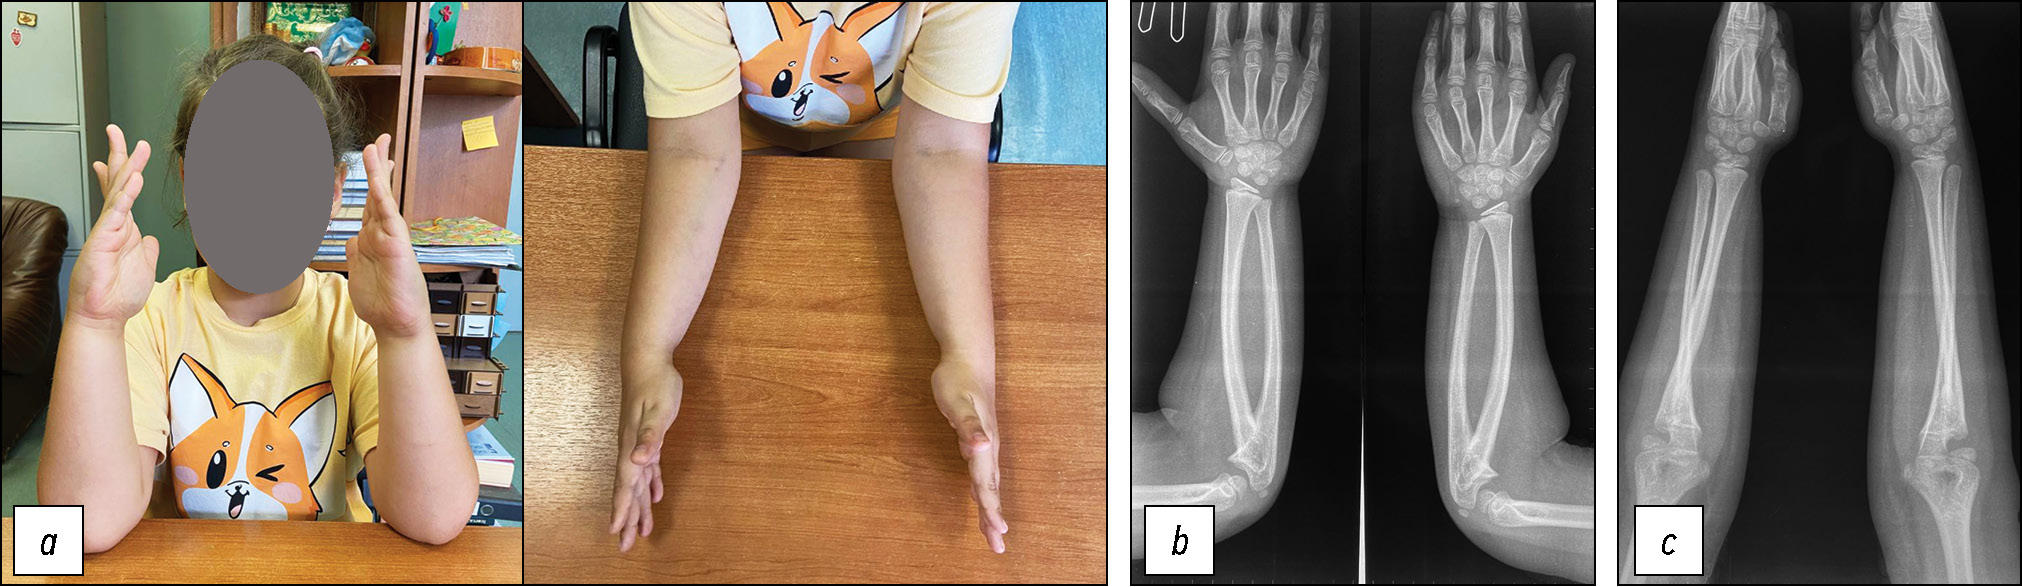

Пациентка П., 15 лет. Первое обращение — в 14 лет, жалобы на нарушение движений в левой верхней конечности, ограничение движений в левом локтевом суставе, нарушение самообслуживания. Диагноз радиоульнарного синостоза слева выставили в 1 год по месту жительства, однако оперативное лечение не было предложено, отметили нарастание деформации и ограничения движений во время роста ребёнка. При первичном осмотре выявлялось следующее: ротационные движения в правом предплечье в полном объёме, слева — отсутствуют, вынужденное установочное положение левой верхней конечности, гиперпронация предплечья до 100 градусов, активная наружная ротация отсутствует, положительная «проба трубача» слева, пальпаторно отмечается подвывих головки локтевой кости (рис. 6, a). На рентгенограммах — проксимальный радиоульнарный синостоз протяжённостью до 6 см, саблевидная деформация лучевой кости, нарушение оси в дистальной трети, укорочение локтевой кости, нарушение костно-суставных взаимоотношений в лучезапястном суставе, головка локтевой кости в состоянии подвывиха (рис. 6, b). Применение вмешательства только на зоне синостоза в данном случае является недостаточным из-за тяжести деформации, старшего возраста ребёнка и протяжённости синостоза, поэтому принято решение провести оперативное вмешательство по комбинированной методике с дополнительной остеотомией лучевой кости (рис. 6, с).

Рис. 6. Пациентка П.: а — внешний вид пациентки (декабрь 2022 г.); b — рентгенограммы при госпитализации; с — оперативное вмешательство на левой верхней конечности (февраль 2023 г.). Дата согласия законного представителя на публикацию — 10.12.2022 г.

Fig. 6. Patient P.: a, appearance of the patient (December 2022); b, radiographs at the time of hospital admission; c, surgical intervention on the left upper limb (February 2023). Informed consent for publication was obtained from the legal representative on December 10, 2022.

В послеоперационном периоде пациентка отметила отсутствие активного разгибания первого пальца левой кисти, на консультацию приглашён невролог. По результатам УЗ-исследования поверхностной и глубокой ветви лучевого нерва не выявлено нарушения их анатомической целостности, но обнаружено интимное прилежание глубокой ветви лучевого нерва к остеотомированной лучевой кости. Невролог назначил спазмолитики, витамины группы В в комплексе, L-карнитин курсом на 2 недели. Через 12 дней после операции симптомы невропатии лучевого нерва полностью регрессировали. Через 8 недель на рентгенограмме зона остеотомии через синостоз в стадии консолидации, однако зона остеотомии лучевой кости не консолидирована, начата активная разработка движений в локтевом суставе. Выполнено удаление фиксирующих спиц, пластина и винты оставлены до окончания консолидации зоны остеотомии лучевой кости. Проводилась консервативная терапия препаратами кальция и витамина D. На плановой консультации через полгода — замедленная консолидация зоны остеотомии лучевой кости, на рентгенограммах отмечается увеличение муфты костной мозоли вокруг зоны сращения, остеосинтез стабилен, подвижности отломков нет (рис. 7, a), состояние коррекции левого предплечья сохраняется (рис. 7, b). Проведена операция: удаление металлоконструкции, остеопластика скользящим аутотрансплантатом зоны замедленной консолидации по Хахутову (рис. 7, с), наложена гипсовая лонгета, начат период наблюдения за сращением и перестройкой трансплантата.

Рис. 7. Пациентка П.: а — замедленная консолидация зоны остеотомии левой лучевой кости; b — внешний вид пациентки перед удалением металлоконструкции и остеопластики, левое предплечье сохраняет положение коррекции (функционально выгодное положение); с — рентгенография после удаления металлоконструкции и остеопластики по Хахутову. Дата согласия законного представителя на публикацию — 10.12.2022 г.

Fig. 7. Patient P.: a, delayed consolidation of the osteotomy site in the left radius; b, clinical appearance of the patient prior to hardware removal and osteoplasty; the left forearm maintains the corrected position, functionally favorable; c, radiograph after hardware removal and osteoplasty according to Khakhutov. Informed consent for publication was obtained from the legal representative on December 10, 2022.